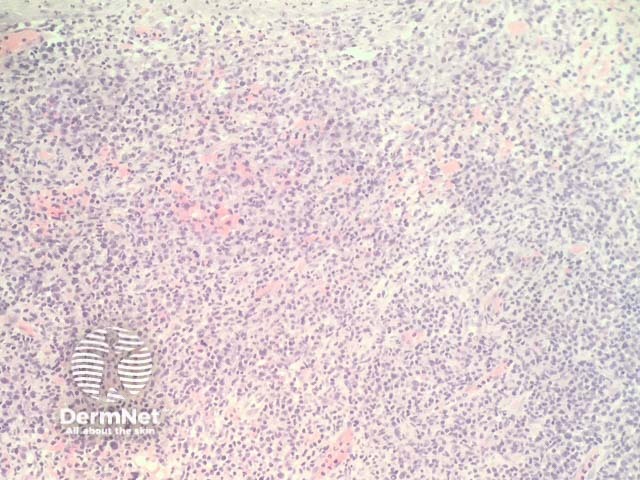

Tumour stage: when tumours start to form clinically, histopathology shows a much denser dermal infiltrate (figure 4). There may be no exocytosis of lymphocytes in this stage. Transformation to large cells may occur (figure 5).

Figure 4